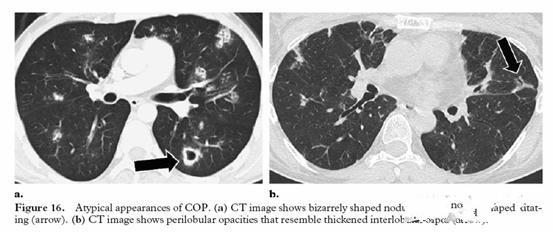

标题: 下边是一例不典型间质性肺炎的ct,大家看看和本例有什么